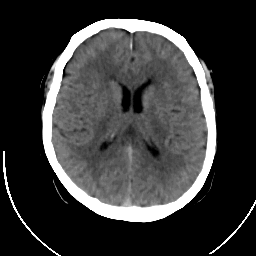

CT Study #1 -- Slice #13

[Home][Help][Clinical][Tour 1] Slice 13